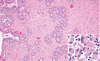

What are the molecular and morphologic changes of the image? ( MDx)

Clinical history and signs: 3 week old puppy, anorexia, dypsnea, abd pain upon palpation, normal rectal temperature

Multifocal, acute renal necrosis and hemorrhage or necrohemorrhagic nephritis

What is the etiology?

Clinical history and signs: 3 week old puppy, anorexia, dypsnea, abd pain upon palpation, normal rectal temperature

Canine herpesvirus-1 (CHV-1)

- red spots are from the virus targeting endothelium

What is the pathogenesis?

Clinical history and signs: 3 week old puppy, anorexia, dypsnea, abd pain upon palpation, normal rectal temperature

Transmission CHV-1 to pup at birth >incubation period of up to 1 week > virus replicates at temperature lower than 37C (98.6F) > endothelial cell tropism > multifocal necrosis in numerous organs